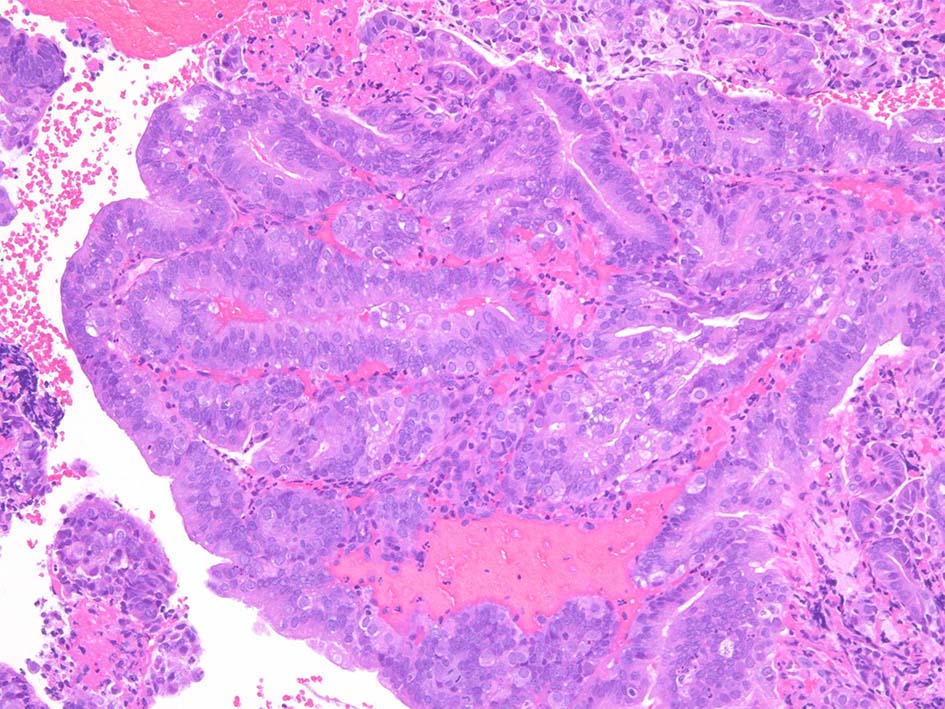

INI1-tumor.jpg INI1-deficient tumor.jpg

Malignant rhabdoid tumor